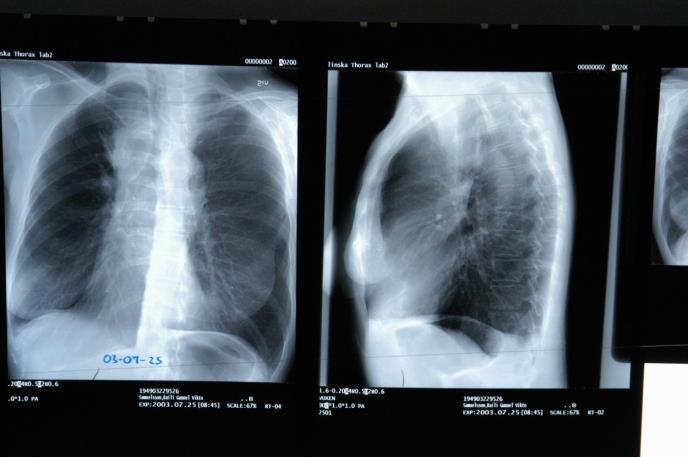

OVE GODINE JE 25 ODSTO MANJE LJUDI OBOLELO OD RAKA PLUĆA! Od te bolesti svake godine umre 4.600 Srba

Procene pokazuju da je u Srbiji tokom 2020. godine, broj novodijagnostikovanih pacijenata od karcinoma pluća bio manji za 25 odsto u odnosu na 2019. godinu. To znači da više od 1.000 ljudi nije dijagnostikovano zbog pandemije izazvane virusom COVID- 19.

Aktuelna epidemija COVID-19 u Srbiji doživljava svoju kulminaciju, pa je sva pažnja opravdano prebačena na pacijente zaražene korona virusom. I pored toga što je percepcija zdravstvenih institucija promenjena, problem ostalih pacijenata ne bi trebalo da padnu u senku. Osobe koje imaju neko maligno oboljenje svakako su u povećanom riziku od COVID– 19 infekcije, a pogotovu oni koji imaju karcinom pluća, najčešći i najsmrtonosniji malignitet kako u svetu, tako i u našoj zemlji. Srbija zauzima neslavno drugo mesto u Evropi po smrtnosti od karcinoma pluća, dok broj obolelih raste svake godine. Od karcinoma pluća godišnje u Srbiji oboli više od 6.000, a umre 4.600 osoba. U proseku, kod 16 osoba dnevno se dijagnostikuje ova vrsta raka, dok na žalost svakodnevno 13 naših građana izgubi bitku sa ovom teškom bolešću.